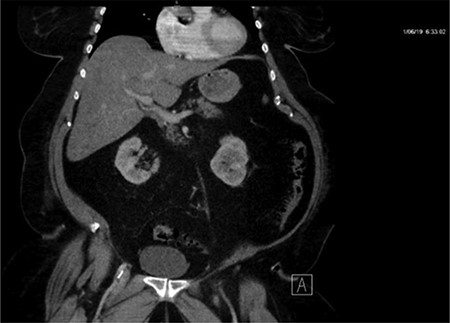

Repeat CT demonstrated a large amount of air within the liver parenchyma (Figs 2, 4, 6). Unfortunately, shortly after the repeat CT, the patient progressed to septic shock with cardiovascular collapse and was not able to be resuscitated with full advanced cardiac life support (ACLS) protocol. She expired within 16 h of initial presentation and within 24 h of symptom onset. Final blood culture results were positive for Clostridium perfringens.

Repeat imaging taken 13.5 h later which depicts many air bubbles in the liver parenchyma.